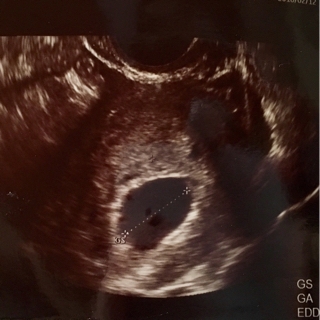

初診…2016年2月12日

胎嚢 21.4mm

内診、胎嚢の大きさのの割に中に見えるものはなし